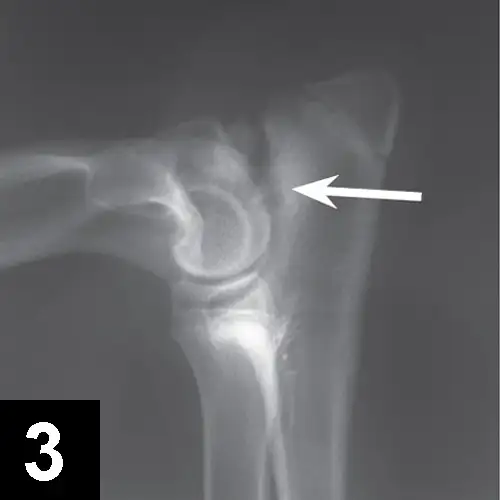

Elbow dysplasia is an umbrella term for several conditions (eg, ununited anconeal process [UAP], medial coronoid disease [MCD], osteochondrosis [OC]/OCD, incongruency) resulting in OA. Most patients are affected by only 1 or 2 of these conditions at the same time (eg, fragmented medial coronoid process, humeral OCD). The causes are multifactorial; genetic and environmental factors are involved. Dogs present with unilateral or bilateral lameness or stiffness of the forelimbs with effusion, pain, and decreased range of motion of the elbow. In dogs older than 5 months of age, radiographs of the joint may show a radiolucent line in the anconeal process (ie, UAP; Figure 3), an articular defect in the medial aspect of the humeral condyle (ie, OC, OCD; Figure 4), sclerosis and blunting of the medial coronoid process (ie, MCD), degenerative changes, or joint incongruency.

Figure 3.

Mediolateral radiograph of the elbow in a 7-month-old German shepherd dog with joint effusion and pain of the elbow. A radiolucent line (arrow) can be observed between the anconeal process and proximal ulna, consistent with UAP.